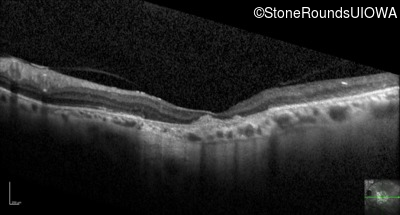

Optical Coherence Tomography - Right - 20/80

Exemplar / OCT Stack

OCT Stack